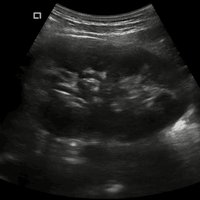

Konvexsonde (C5-2Ks) 3,3 MHz 2 - 5 MHz R50 Abdomen, Gynäkologie, Geburtshilfe, Urologie